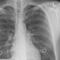

En Italia, médicos realizaron los primeros trasplantes de corazón de donantes que murieron tras contagiarse de Covid-19.

Se trata de dos corazones; los cuales, fueron trasplantados -con éxito y sin contagio- a pacientes sin anticuerpos del virus.